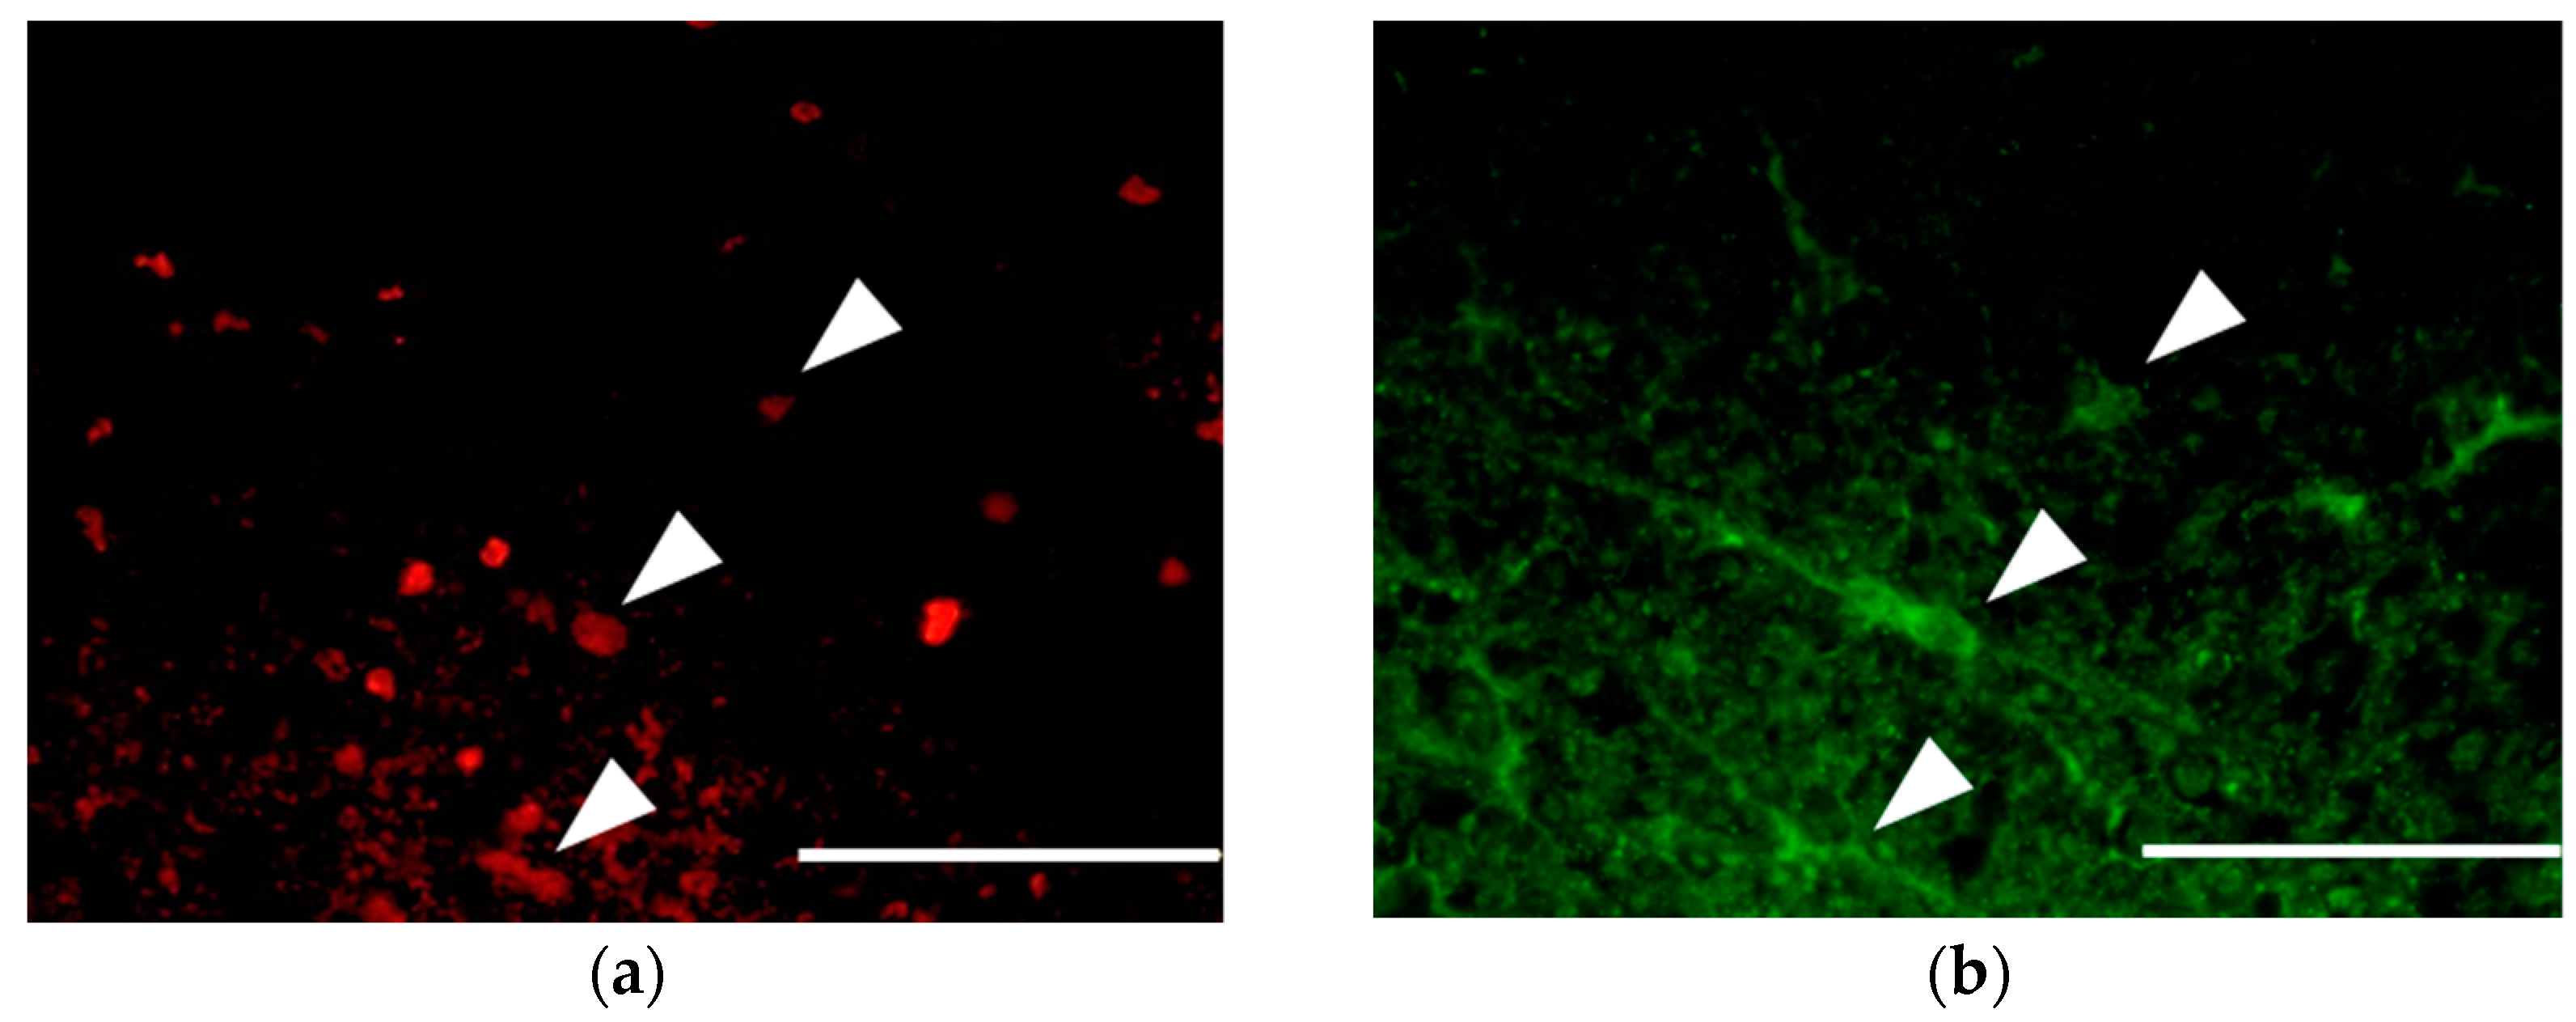

3.3. Survival and Proliferation of Oligodendrocyte Precursor Cells (OPCs)